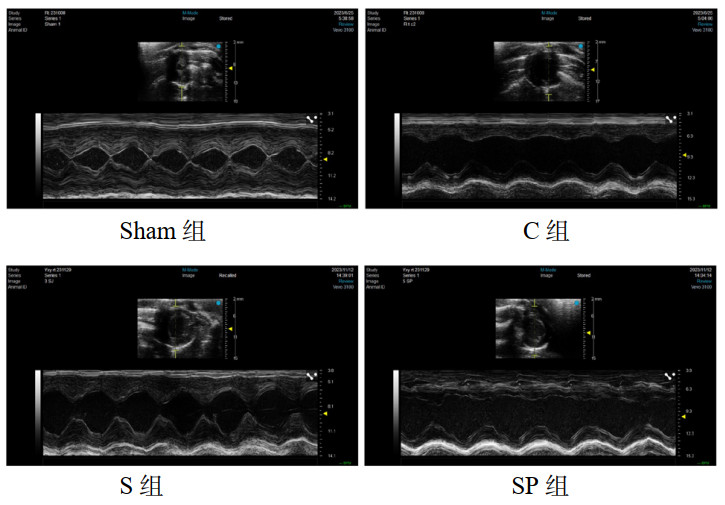

1.2.3 心脏超声检查术后20 h,大鼠采用异氟烷吸入麻醉后进行心脏超声检查评估心功能,采用RMV 707B型高频超声探头,频率25~30 MHz。大鼠取仰卧位,胸骨旁左心室短轴乳头肌切面采集M型超声心动图,记录大鼠的左室舒张末容积(left ventricular end-diastolic volume, LVEDV)、左室射血分数(left ventricular ejection fraction, LVEF)、左室收缩末容积(left ventricular end systolic volume, LVESV)以及左室短轴缩短率(left ventricular fractional shortening, LVFS)。

2 结果 2.1 大鼠心脏超声检查C组LVEDV和LVESV均高于假手术组,而左心室射血分数(LVEF)和左心室缩短率(LVFS)则低于sham组(P < 0.05);而S组较C组LVEF、LVFS升高,差异具有统计学意义(P < 0.05),但LVESV虽较C组有所下降,但差异无统计学意义(P > 0.05)。而SP组较S组的LVESV升高,具有统计学意义(P < 0.05);LVEF、LVFS、LVEDV下降,但差异无统计学意义(P > 0.05)。见表 1。大鼠CLP术后20 h心脏超声结果见图 1,sham组大鼠左心室结构正常,心室腔近椭圆形,侧壁显示清楚,室壁运动正常;C组为脓毒症组,可见大鼠左心室心腔明显扩大,室壁运动减弱,收缩功能下降。

| 注:sham组为假手术组,C组为CLP模型组,S组为CLP+Sirt1激动剂组,SP组为CLP+sirt1激动剂组+PGC-1α抑制剂组 图 1 各组大鼠心脏超声结果 Fig 1 Ultrasound images of rat hearts in each group |